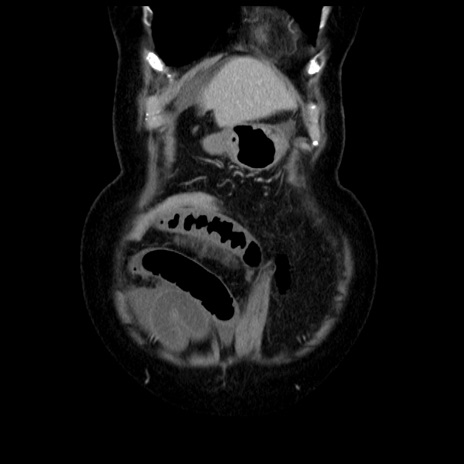

横断像